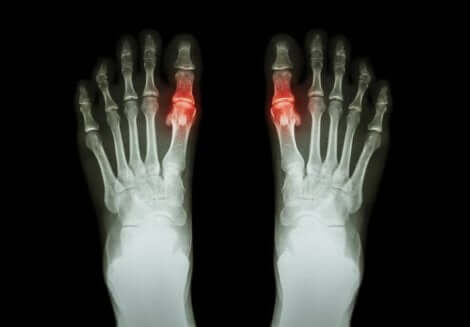

يميل هذا المرض إلى الظهور في صورة ألم وصعوبة في تحريك المفاصل المصابة. في بعض الحالات، تشمل الأعراض التصلب والورم في نفس المنطقة.

يمكن للحالة أن تصيب مفصل واحد أو عدة مفاصل في نفس الوقت. ويمكن أن تكون متناظرة أو غير متناظرة.

لكل نوع سماته الخاصة، وتختلف أيضًا المدة التي تستمر فيها الأعراض من نوع لآخر. على سبيل المثال، فالتهاب المفاصل الروماتويدي نوع متناظر يصيب المفاصل الصغيرة، كتلك الموجودة في الأصابع.

على الجانب الآخر، النقرس من الأنواع غير المتناظرة التي تميل إلى إصابة مفصل واحد.